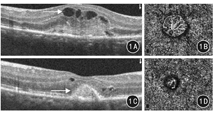

与治疗前比较,wAMD组治疗后miRNA-126相对表达量及BCVA明显增加,VEGF-A及CMT、CNV面积均明显降低,差异均有统计学意义(P值均<0.01)。见表4及图1。

应用OCTA技术检测黄斑中央区视网膜厚度(centre macular thickness, CMT)及脉络膜新生血管(choroidal neovascularization, CNV)面积。治疗前选择血流成像模式,嘱患者注视设备中自带蓝色视标,扫描范围为黄斑区3 mm×3 mm。扫描方式为水平及垂直方向线性扫描,定位病灶后手动调整分层界限以保留清晰度最高的图片,应用设备自带软件系统进行图像分析,自动计算输出CMT,以μm为单位;CNV面积则需先手绘需要测量的病变区域,然后系统会自动提取范围内的异常血流信号,并自动计算出其面积,以mm2为单位。治疗后1个月选择追踪定位模式扫描,扫描范围和扫描方式同治疗前。检测由经过正规培训的、从事眼底病诊断工作10年以上的2名副主任医师按照标准流程操作,检测结果取平均值。